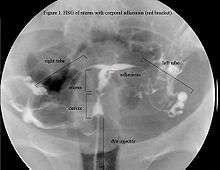

In an attempts to estimate the prevalence of AS in the general population, it was found in 1.5% of women undergoing hysterosalpingography HSG,[22] and between 5 and 39% of women with recurrent miscarriage.[23][24][25]

The history of a pregnancy event followed by a D&C leading to secondary amenorrhea or hypomenorrhea is typical. Hysteroscopy is the gold standard for diagnosis.[8] Imaging by sonohysterography or hysterosalpingography will reveal the extent of the scar formation. Ultrasound is not a reliable method of diagnosing Asherman's Syndrome. Hormone studies show normal levels consistent with reproductive function.